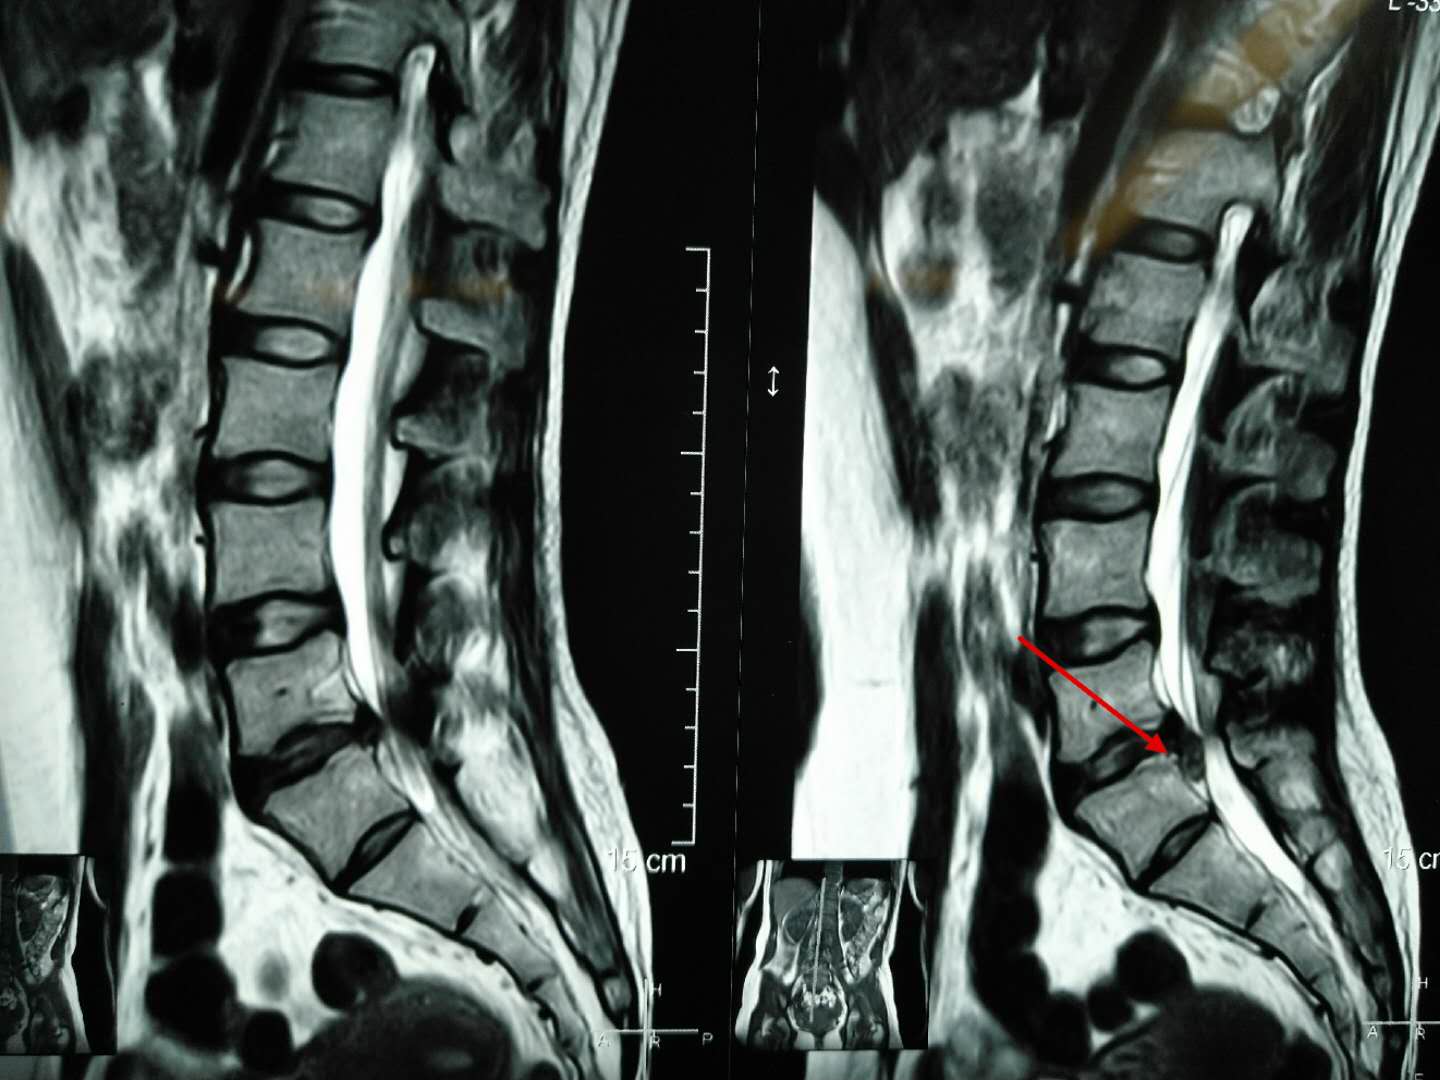

从术前的腰椎磁共振我们可以看到腰椎向下脱垂游离的巨大间盘突出,压迫右侧神经根,我们给她做了后路脊柱内镜下腰椎间盘摘除术。

术后第二天复查腰椎磁共振我们可以看到脱垂的间盘组织被完整的摘除,术后当即患者的症状就消失了,可谓立竿见影。